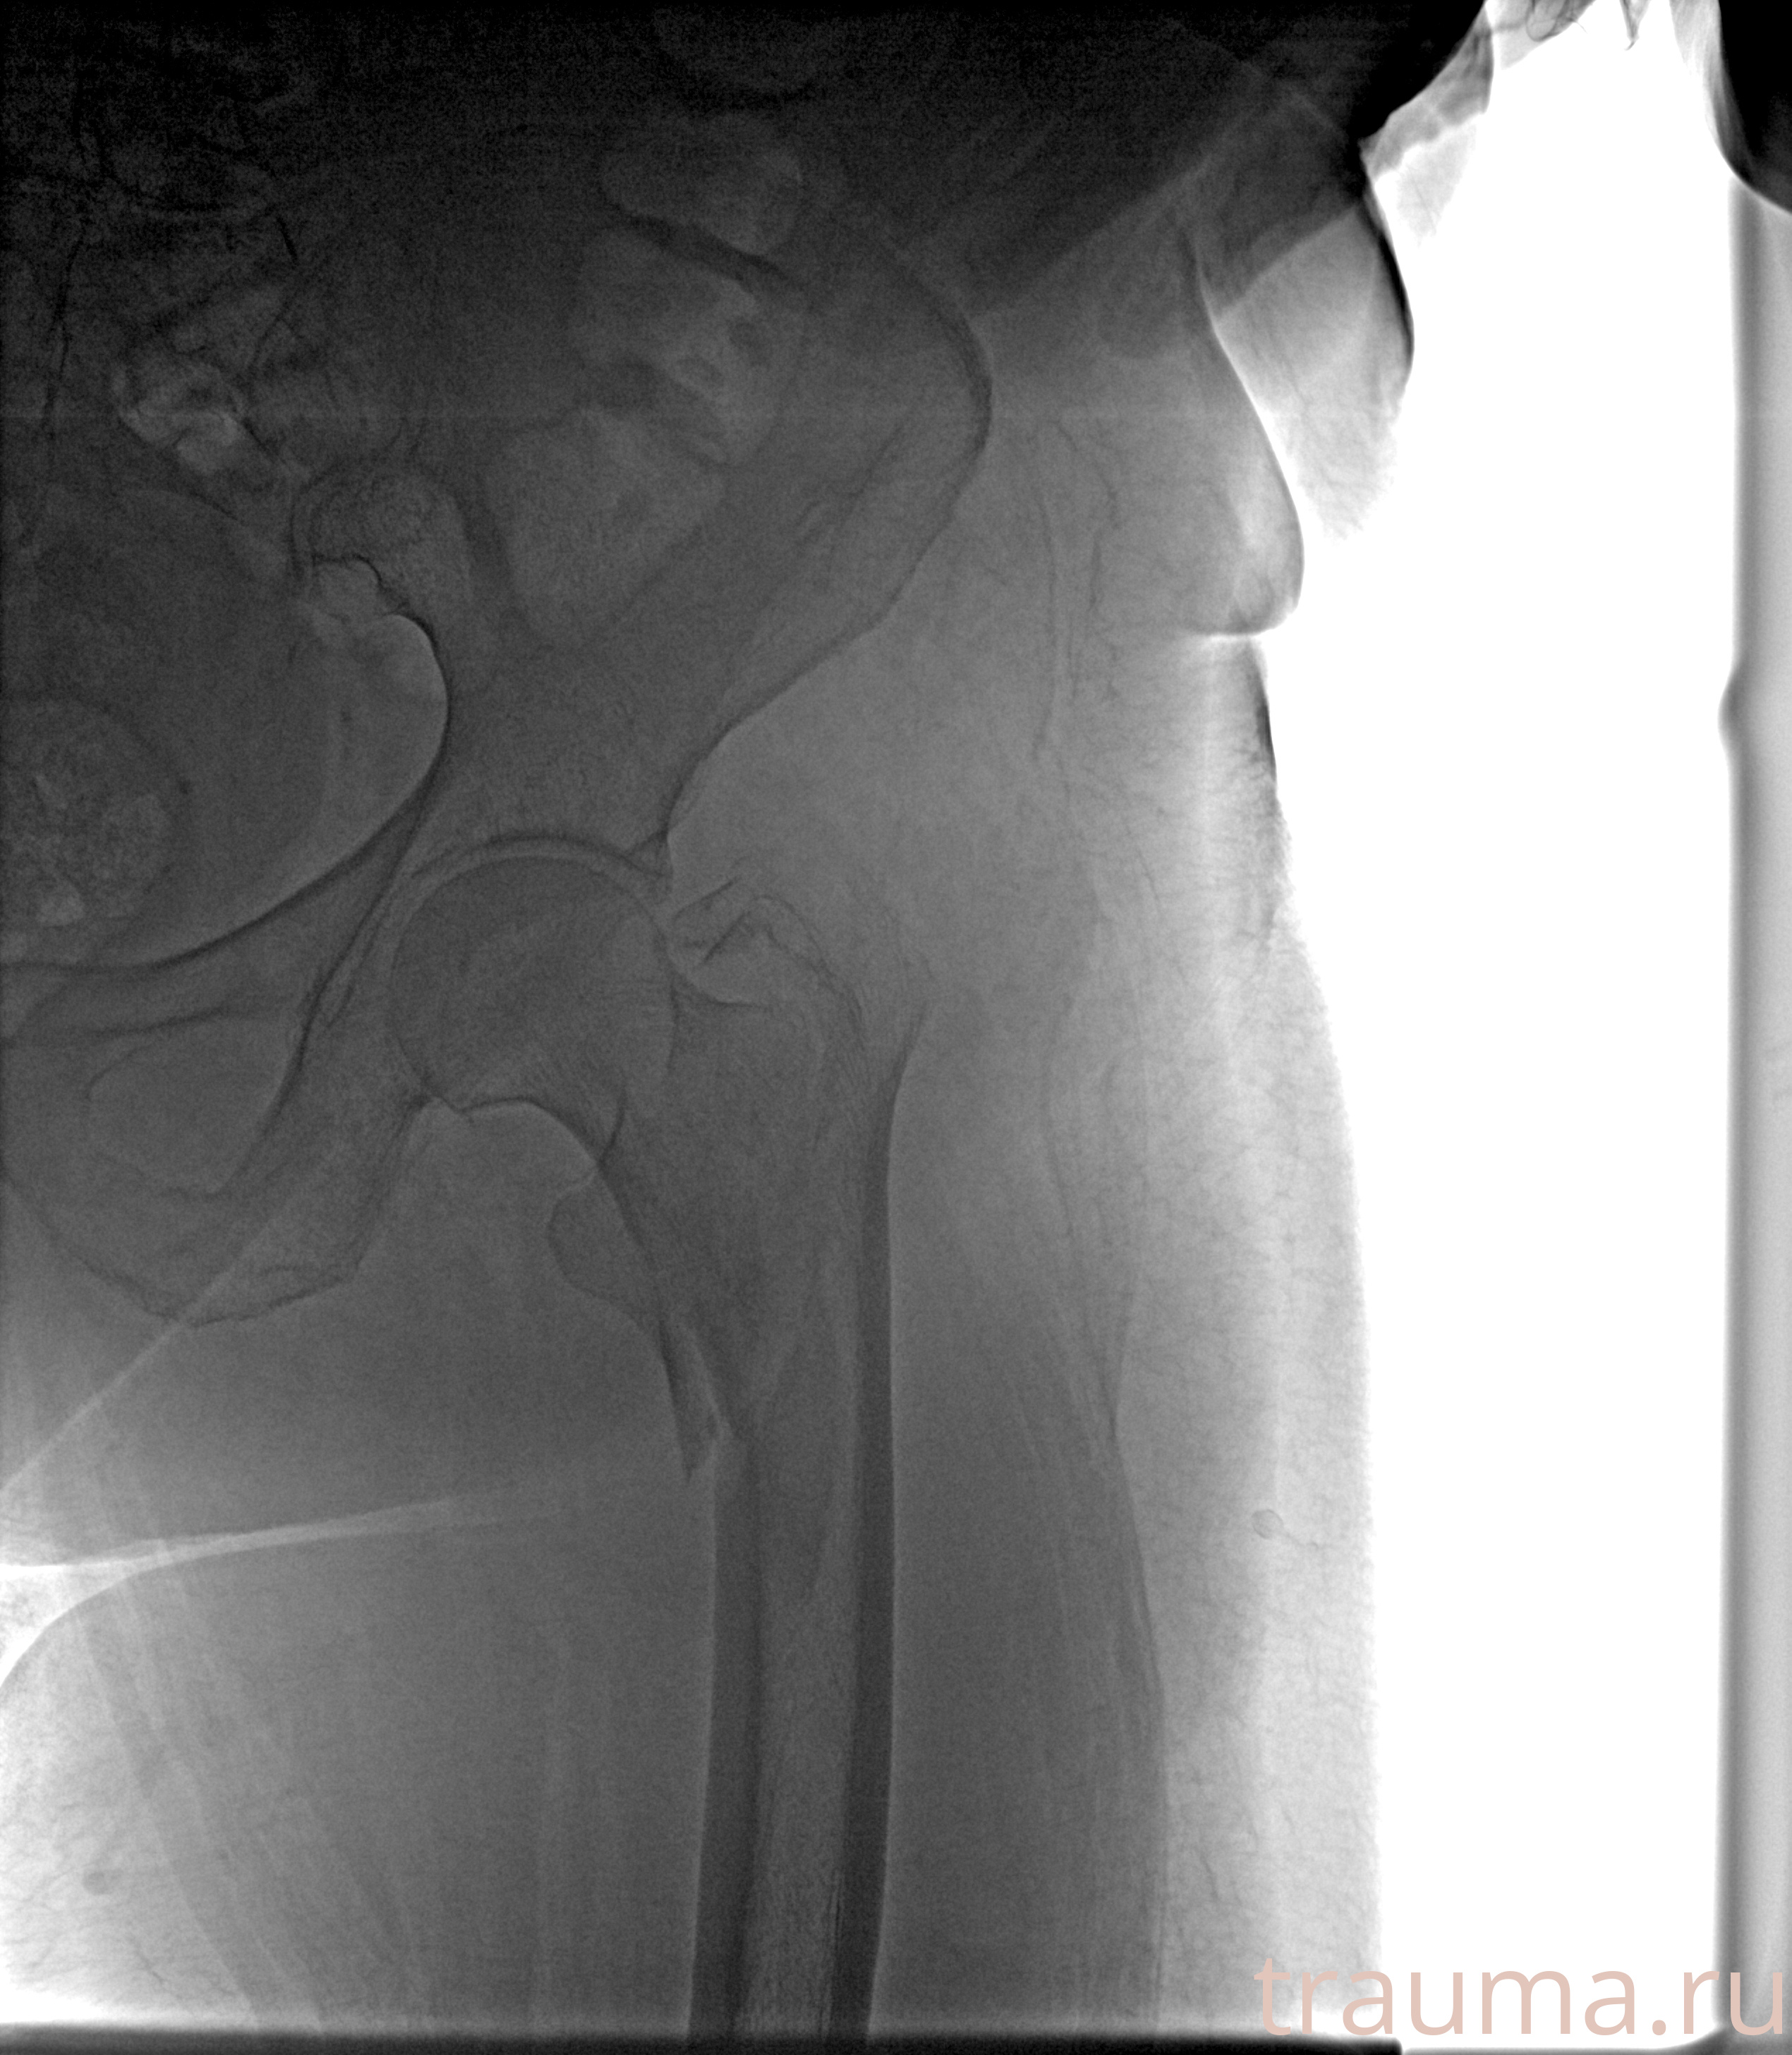

Рентген на дому: по вашему адресу приезжает врач-рентгенолог, травматолог-ортопед с мобильным рентгеновским аппаратом, проводит диагностику травмы или заболевания, делает необходимые рентгенограммы, дает рекомендации по дальнейшему лечению. Получить качественные снимки в домашних условиях возможно благодаря уникальной методике, разработанной МосРентген Центром для института  Склифосовского